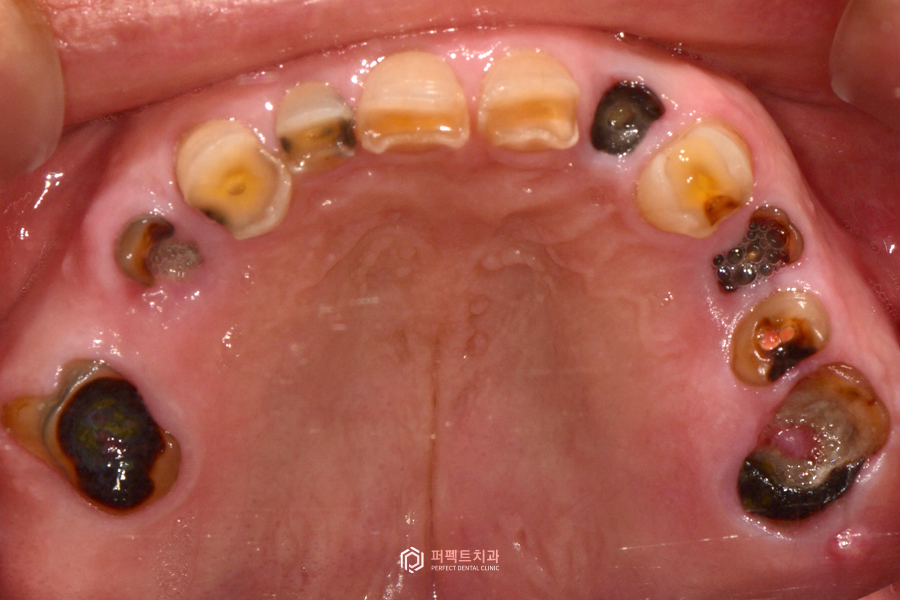

초진 구강사진

실제 구강 내 사진을 보시면 없는 치아들이 많고, 남아있는 치아도 모두 썩어있는 것을 보실 수 있습니다. 그리고 중요한 점은 치아가 계속 없이 지내게 되면 치아가 닳고 썩어서 교합이 무너진 상태입니다.

무너졌다는 것은 원래 씹는 높이가 정상이었는데 닳고 부러지면서 교합이 낮아져 있는 경우입니다. 이렇게 낮아진 교합 높이를 올리는 수복까지 다같이 이루어져야 해서 난이도가 높은 케이스에 해당하는 경우입니다. 이런 경우는 어떻게 해야 되냐면 임시치아 혹은 임시틀니를 이용해서 그 높이를 맞춘 다음에 거기에 맞는 최종보철을 만든 그런 경우라고 보시면 될 것 같습니다.